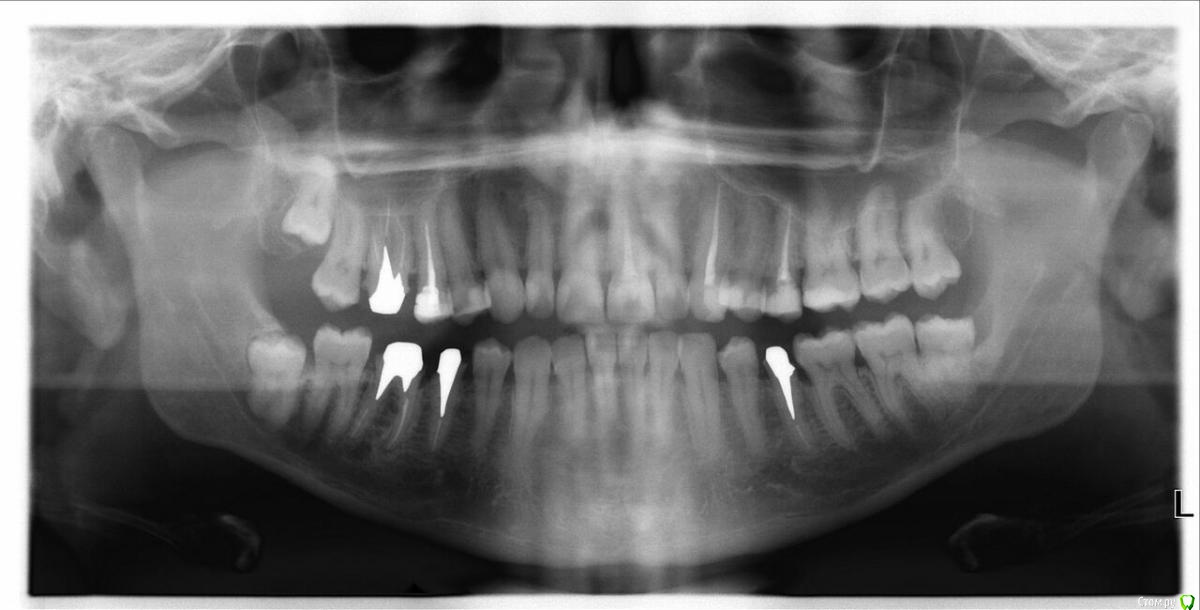

solsystem Опубликовано 30 августа, 2018 Поделиться Опубликовано 30 августа, 2018 Добрый день! Решил плотно заняться зубами (пришло время заменить все временные коронки на постоянные) и побывал у двух врачей, которые предлагают разные варианты:1) Необходимо удалить восьмерку слева внизу, чтобы потом постепенно подвинуть 7,6 с помощью цемента и временной коронки. После уже ставить коронку на 5. 2) 8-ки трогать не надо и все коронки встанут без проблем. Хотелось бы услышать Ваше независимое мнение, чтобы определиться какой из вариантов оптимальней. https://www.dropbox.com/s/89uxyb2aqkfq42x/%D1%81%D0%BD%D0%B8%D0%BC%D0%BE%D0%BA.jpeg?dl=0 Ссылка на комментарий

red_butler Опубликовано 6 сентября, 2018 Поделиться Опубликовано 6 сентября, 2018 Восьмой зуб я бы удалил, по поводу перемещения зубов временной коронкой не понял Ссылка на комментарий

solsystem Опубликовано 6 сентября, 2018 Автор Поделиться Опубликовано 6 сентября, 2018 Врач говорит, что после удаления восьмерки нужно будет постепенно двигать 6 и 7. Аргументирует это он тем, что если этого не сделать, то коронка скорее всего не встанет правильно на вкладку и под неё будут попадать остатки пищи. Для этого он планирует периодически наращивать слой цемента между временной коронкой и 6 зубом. Честно говоря я и сам не понял как это будет выглядеть. И у меня тут сразу еще одна проблема назрела, которую я для себя открыл во время прочтения форума. Оказалось, мне поставили серебряные вкладки и при этом оба доктора предлагают мне установить металлокерамику. Но насколько я понял, это может в дальнейшем мне доставить много проблем. Поскольку удалить вкладки будет проблематично, то лучшим вариантом будет установить цельноциркониевые коронки?(Или для этого вопроса лучше создать отдельную тему в другой категории?) Ссылка на комментарий